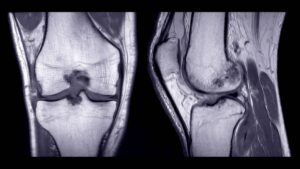

Auf unserer Seite finden Sie umfangreiche Informationen zu orthopädischen Beschwerden und Erkrankungen. Von der Arthrose über Bandscheibenvorfälle bis hin zu Kreuzbandriss und weiteren Sportverletzungen: wir geben Ihnen einen Überblick über die häufigsten orthopädischen Krankheitsbilder, wie sie behandelt werden können und inwieweit ein Bildgebungsverfahren, wie eine (z.B. MRT Knie, Rücken MRT) bei der Diagnose bei der Diagnose unterstützend wirken können.

Viele Betroffene suchen online nach den Ursachen oder Behandlungsmöglichkeiten von Rückenschmerzen, Bänderriss am Fuß oder Bandscheibenvorfall. Einige der orthopädische Beschwerden oder Verletzungen benötigen zu Behandlung eine Bildgebung und Therapie. Alle relevanten Informationen lesen Sie in den jeweiligen Beiträgen.

Unsere Liste zu den häufigsten orthopädischen Problemen ist alphabetisch von A-Z geordnet. So finden Sie schnell und unkompliziert den Beitrag, der Ihnen weiterhilft. Von Krankheiten, über Verletzungen bis hin zu schmerzhaften Zuständen wie Arthrose, Meniskusschaden und Schleimbeutelentzündung – hier finden Sie die wichtigsten Informationen.